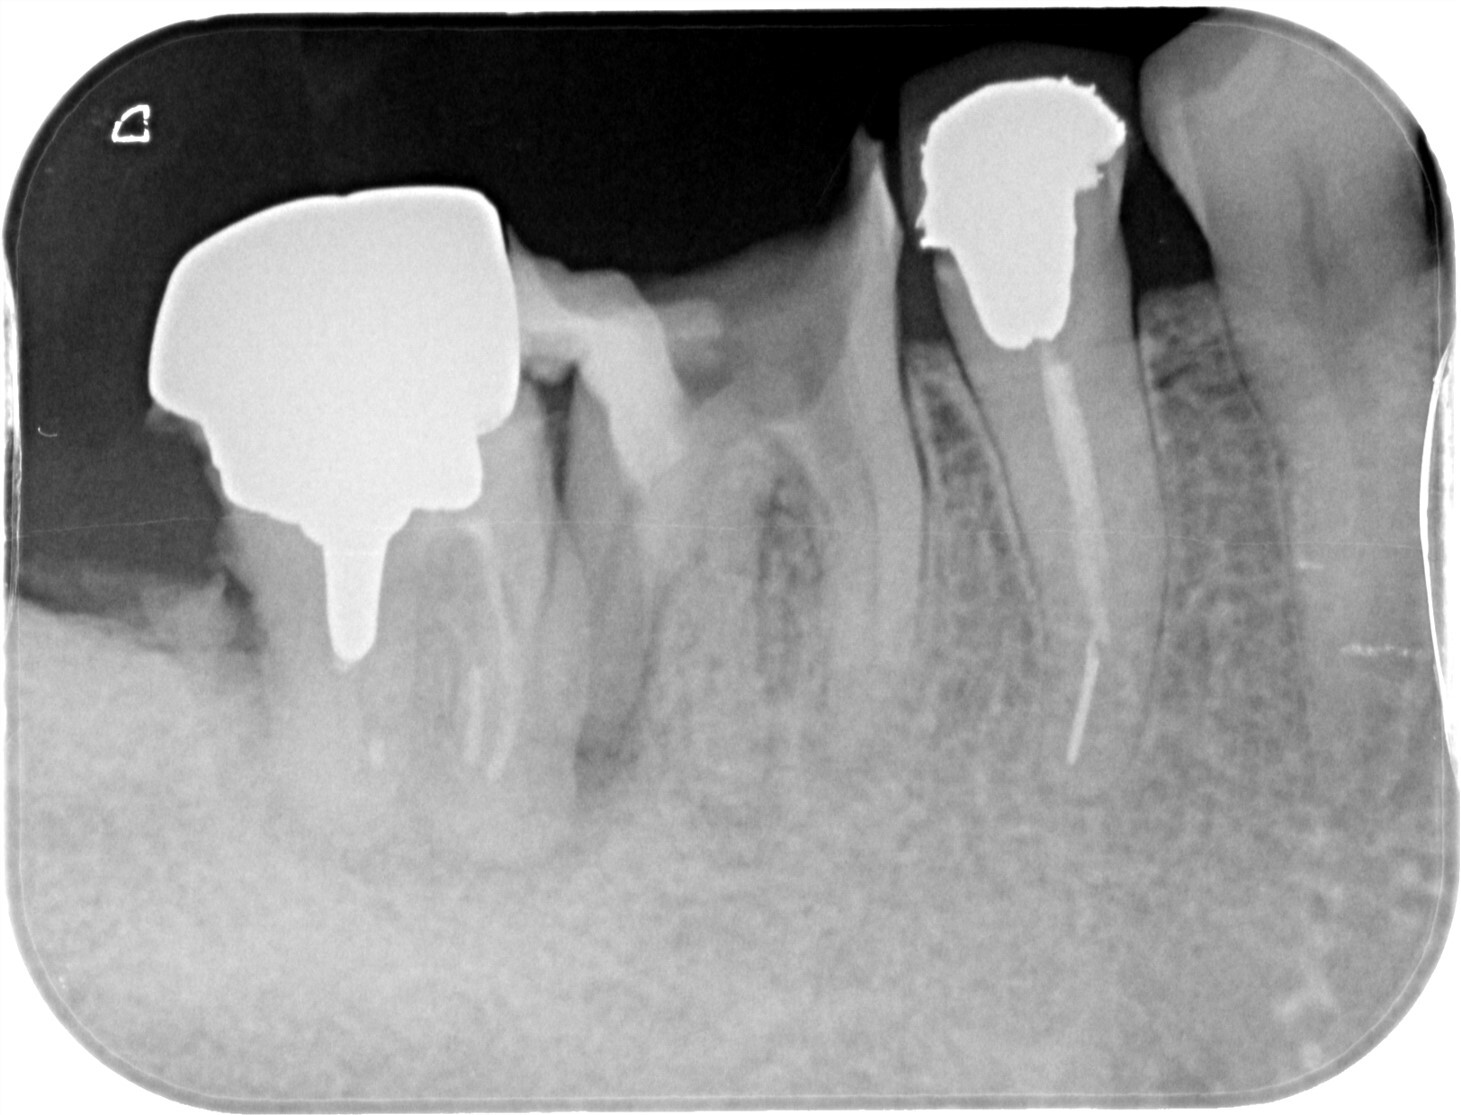

| 主訴 | 過去の治療にて根管充填後、噛むと違和感・痛みが出てきた。一度詰めた薬を撤去してもらったが症状が変わらなかったため来院。 |

| 治療内容 | ラバーダム防湿を行い、マイクロスコープにて根尖部の溢出ガッタパーチャの除去を行いました。 |

CT撮影により根尖部にガッタパーチャの溢出を確認。

拡大視野下にて残存ガッタパーチャを確認しながら過拡大に注意しながら除去。

その後根管充填を行った症例です。ガッタパーチャ除去したことで症状が改善されました。